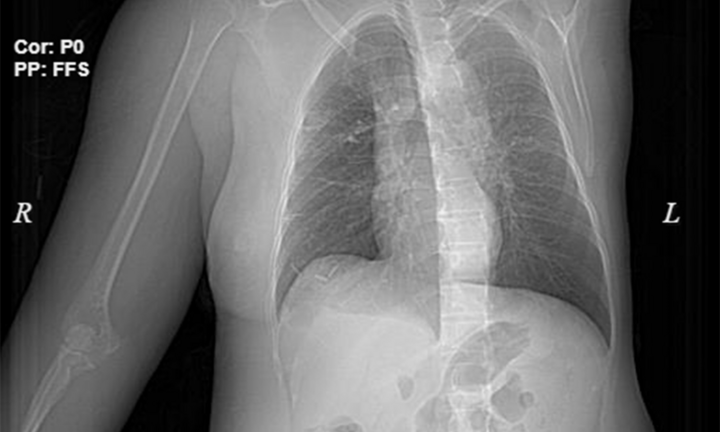

Phát hiện bị ung thư vú từ lâu, nhưng người phụ nữ này không tới viện thăm khám, chỉ ở nhà đắp thuốc nam, do điều trị sai cách nên bệnh của bà càng thêm nặng.